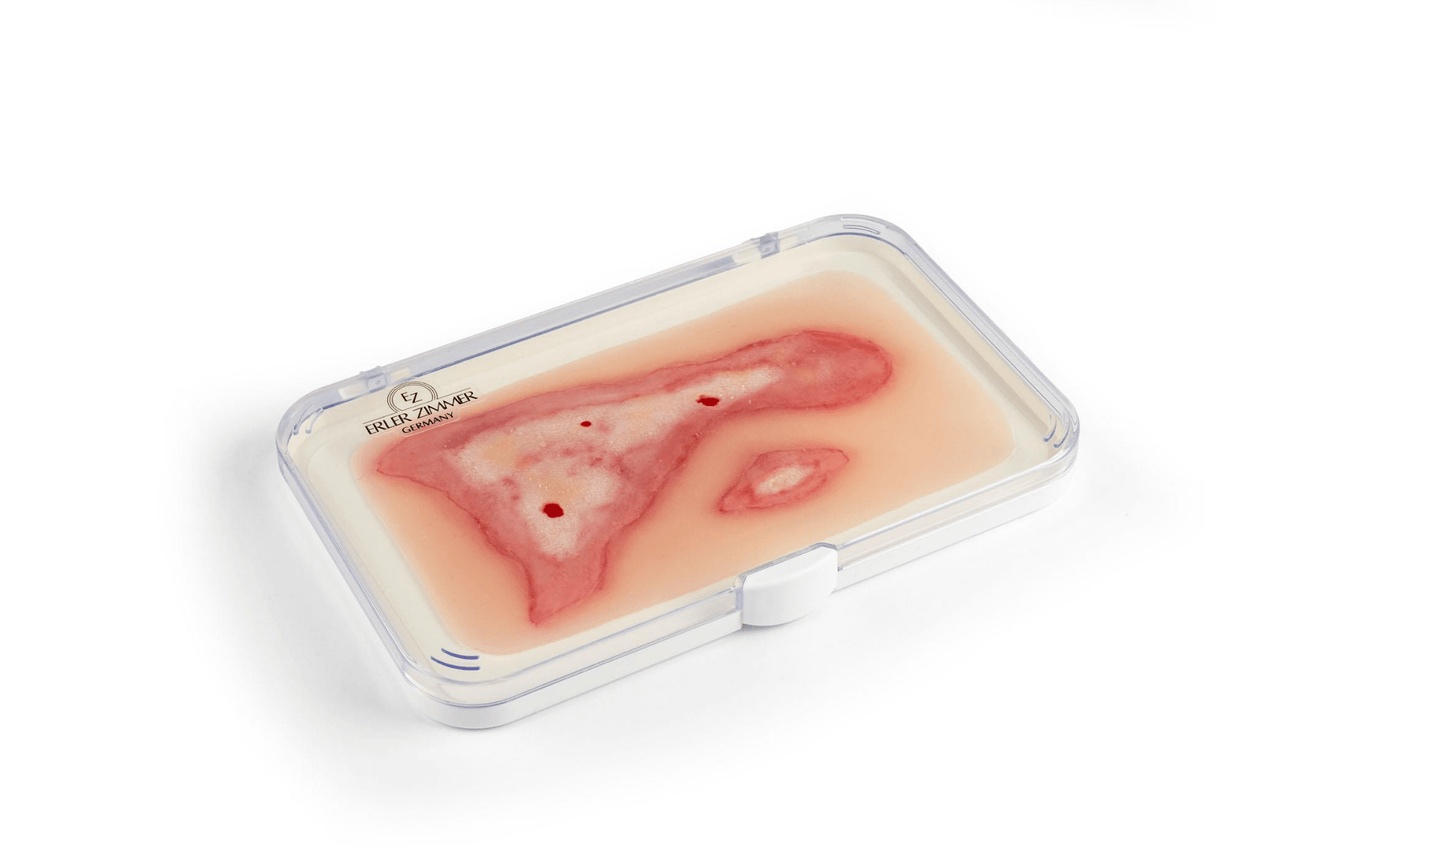

Unsere Wundmoulagen bieten eine äußerst realistische Darstellung verschiedenster Verletzungen und Wunden und sind daher unverzichtbare Hilfsmittel für medizinische Ausbildungen, Notfallübungen und Schulungen. Sie ermöglichen eine präzise und anschauliche Simulation von Verletzungen, die den realen Bedingungen in der medizinischen Praxis entsprechen. Die Moulagen sind aus weichem, hautähnlichem Material gefertigt, das keine Verletzungsgefahr darstellt und eine authentische Haptik bietet.

Durch ihre vielseitige Anwendbarkeit eignen sich die Wundmoulagen für die Übung von Wundversorgung, Verbandstechniken und Notfallmanagement. Sie haften selbstständig an Simulationspatienten oder Puppen, können jedoch bei Bedarf mit speziellem Hautkleber für längere Übungseinheiten befestigt werden. Jede Moulage wird mit einer praktischen Aufbewahrungsbox geliefert, die eine sichere und ordentliche Lagerung ermöglicht.

Realistische Darstellung von verschiedenen Wunden (z.B. Schnitt-, Riss-, Brand- oder Stichwunden)

Inklusive praktischer Aufbewahrungsbox für eine sichere Lagerung